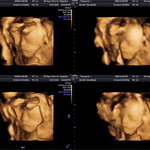

คุณแม่ลูกชาย

Kim cươngคุณแม่ลูกชาย